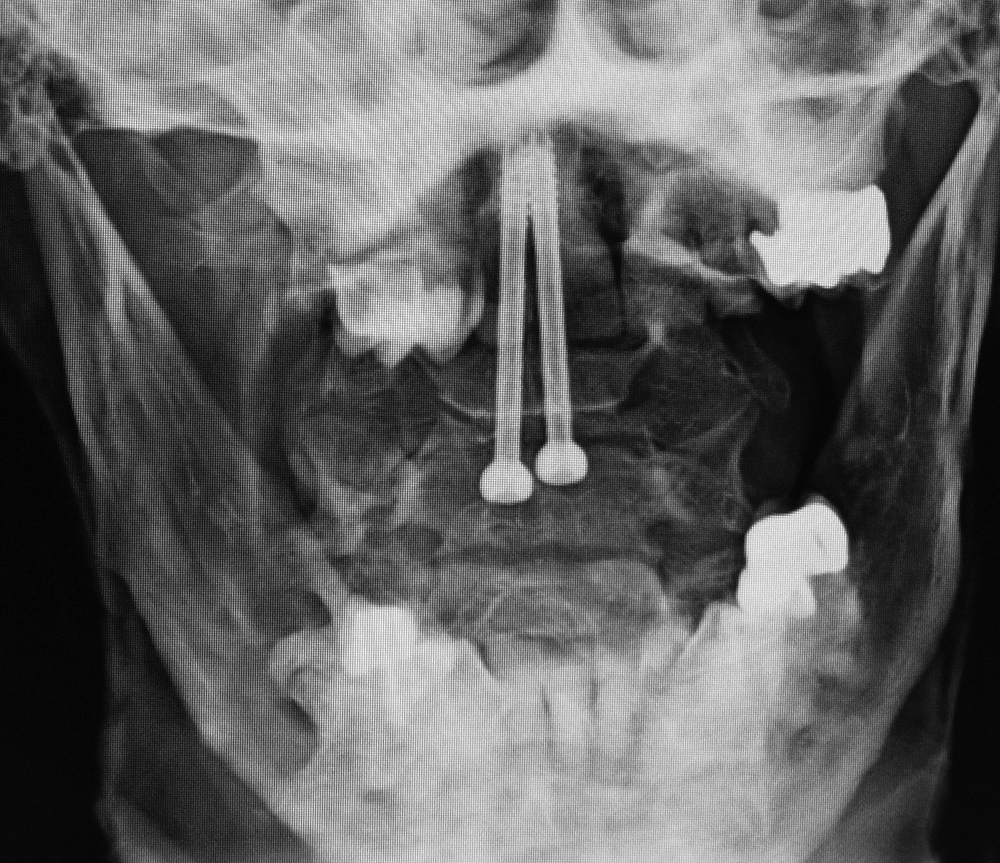

| Two odontoid screws |

| 86 year-old woman with C1 posterior ring and type II dens fractures two months earlier treated with two odontoid (dens) screws. |